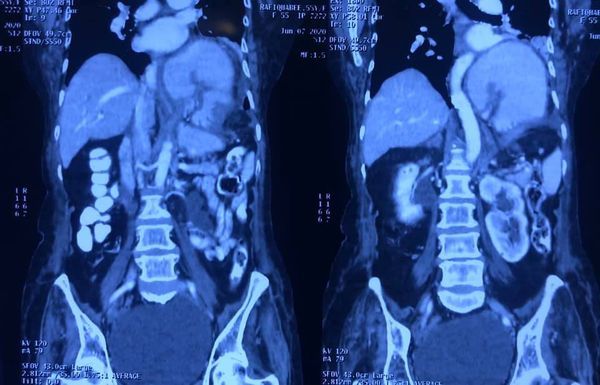

Challenging emergency during the COVID: Child’s A CLD with HUGE gastric varices uncontrolled

Child’s A CLD with HUGE gastric varices uncontrolled by Endoscopic glue and attempted EUS coiling. One salvage option would be TIPSS with balloon vascular occlusion but due to logistics we went for modified sugiura procedure. Splenectomy + Gastro esophageal devascularisation with anterior Gastrotomy and overseeing of gastric varices with pyloroplasty. Images show 1 CECT showing large gastric fundal varices. 2,3,4 Gastro Esophageal devasc 5, 6 Large fundal varices before and after oversewing. 7. Anterior gastrotomy 8. Pyloroplasty. Postoperative recovery was uneventful.